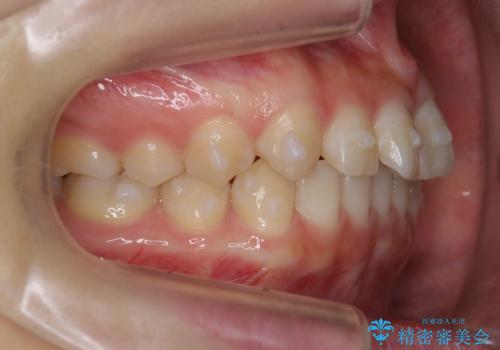

前歯のねじれ 乳歯を残して矯正治療

- 前歯のねじれを気にして来院。

左下に乳歯が残っていましたが、被せ物に穴が空いている状態でした。

乳歯は抜かずに保存的な治療を行いました。

上下の正中が1本分ずれていましたが、ちょうど1本分で目立たず、また、右下の歯が生まれつき少ないことを利用して、最小限の歯の移動にとどめました。

乳歯はまだぐらついたりしていない状態だったため、しっかり虫歯を取り、根の治療も行いました。